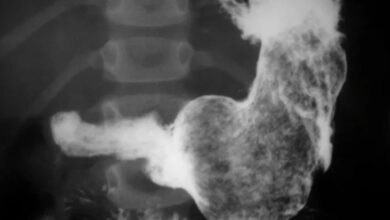

Síndrome de Rapunzel: la historia de la niña de que se arrancaba y tragaba su cabello compulsivamente

Un hospital checo anunció este martes que sus cirujanos retiraron una madeja de pelo del tamaño de un vaso de…